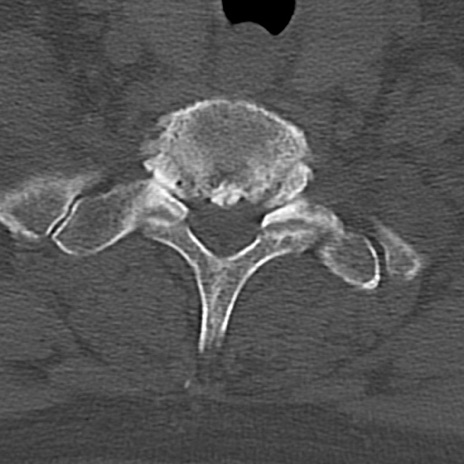

頚椎CT

横断像